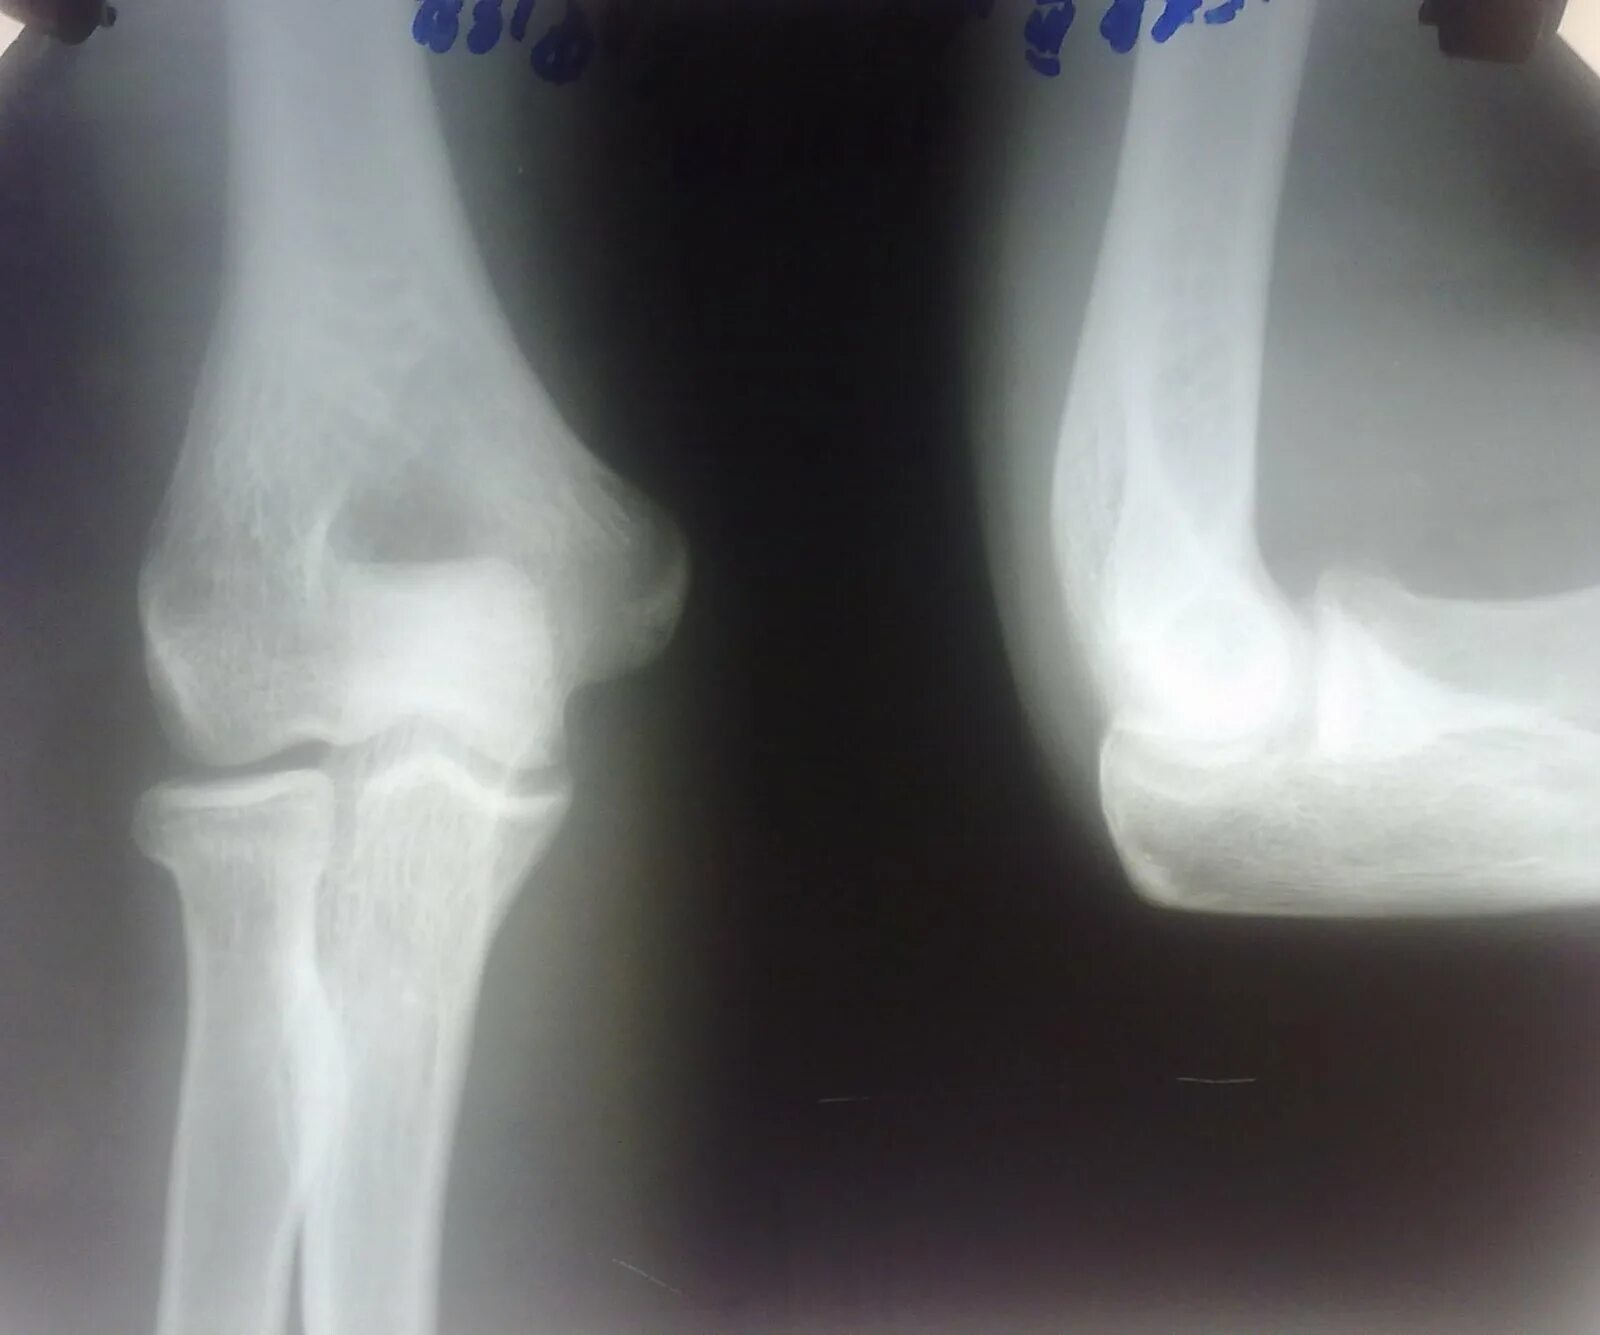

Перелом смещение локтя